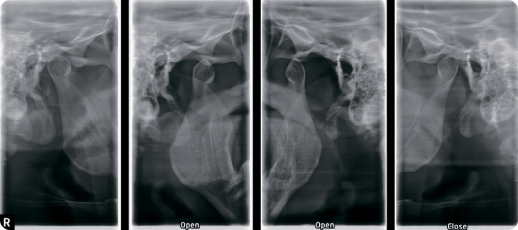

ВНЧС